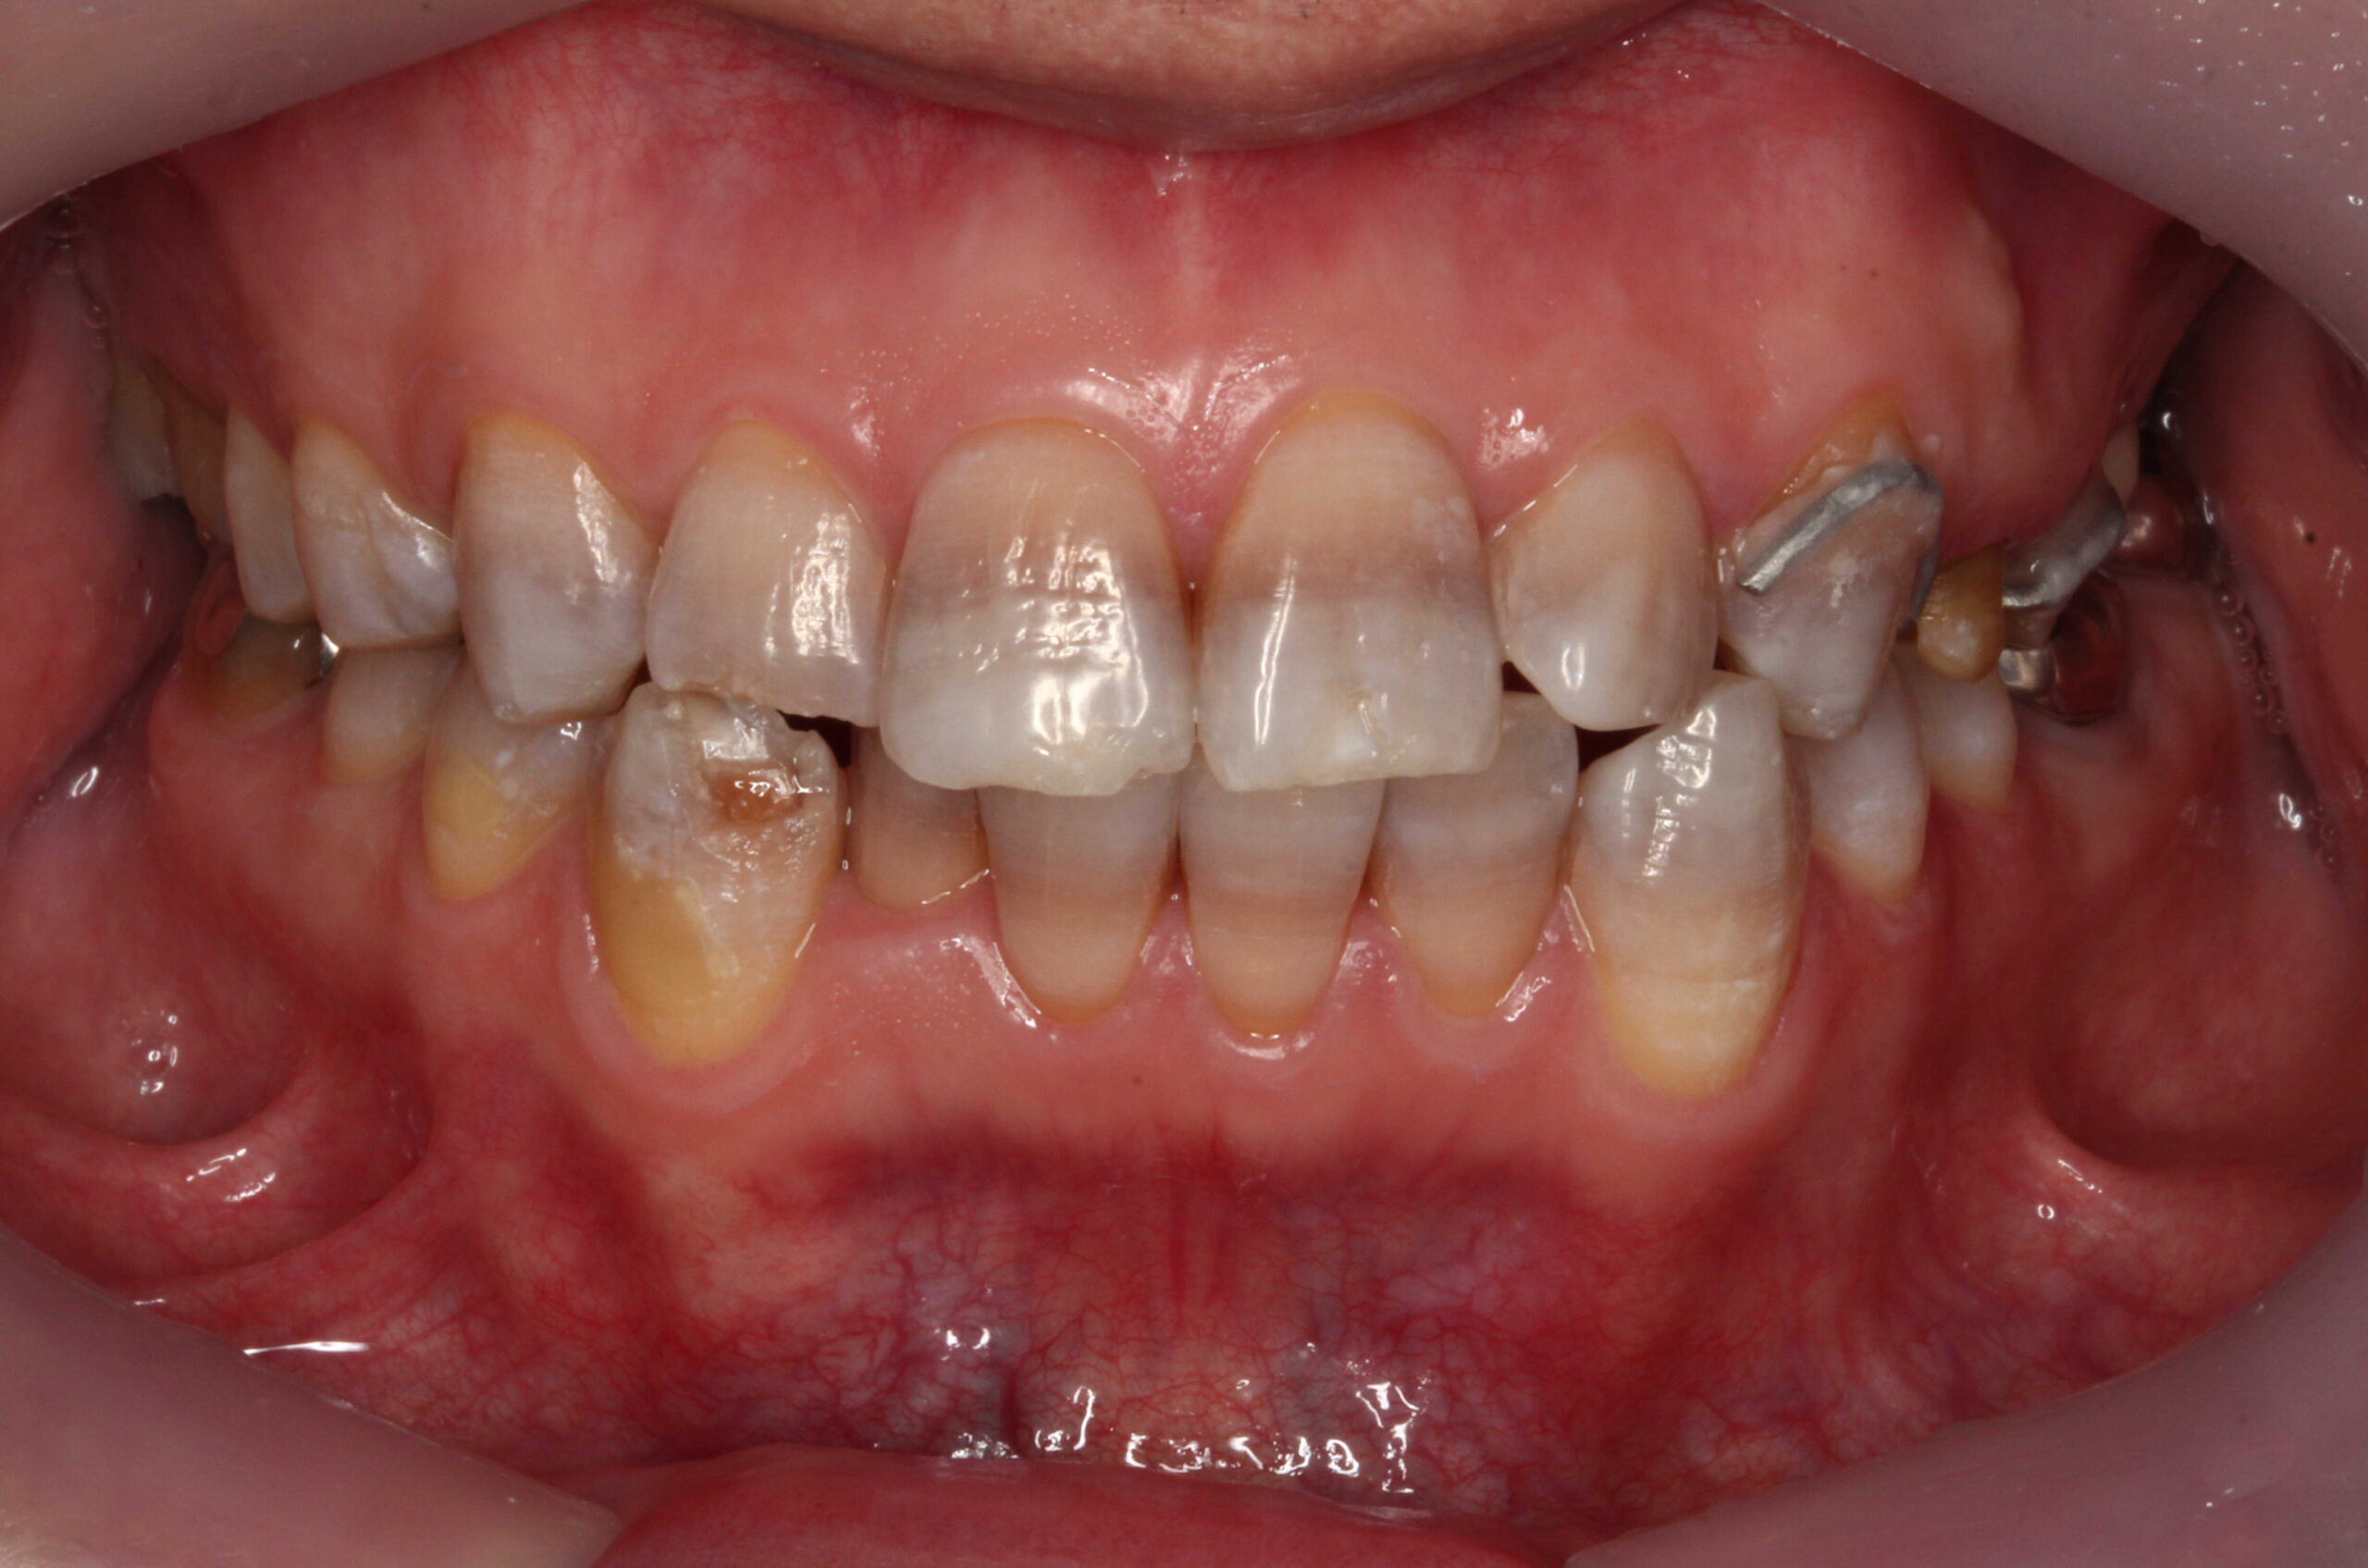

テトラサイクリン歯を他院でセラミッククラウンで被せていた事例

他院にてテトラサイクリン歯を上前歯6本のセラミッククラウンで被せてある症例です。

従来のクラウンの方法では支台になる歯の外周を大きく削ることになってしまいます。

当院でも以前はこのような方法で多くの審美歯科を行っていました。

他院で前歯6本クラウン 当院で右上54、左上45に

削らないラミネートベニア

他院では前歯6本を削ってクラウンで治しています。

患者様は削らない方法で審美的に揃えたいということでご来院されました。

奥の右上54、左上45も削らずに前歯と審美的に揃えたいということで、当院で削らないラミネートベニアで治しました。